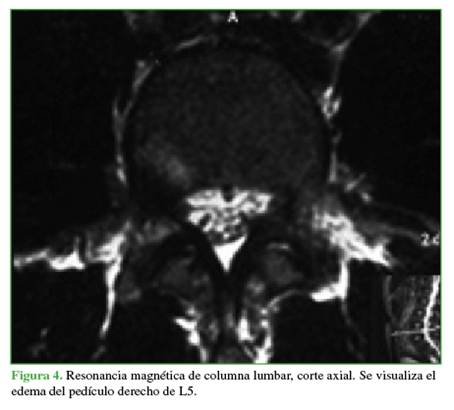

Se tomaron radiografías de columna lumbar, de frente, de perfil y oblicuas que revelaron esclerosis del pedículo derecho y espondilólisis izquierda de L5. La tomografía computarizada mostró, además de la lesión antes descrita, una solución de continuidad en el pedículo derecho, con márgenes escleróticos e hipertróficos (Figuras 1 y 2). En la resonancia magnética, se visualizó un edema en dicho pedículo lumbar (Figuras 3 y 4).

Un rasgo habitual en la pediculólisis es la esclerosis del pedículo, pero aún no resulta claro si esto representa un fenómeno de adaptación anterior a la fractura o si es una consecuencia de ella.9 Esta esclerosis unilateral le da el aspecto de vértebra anisocórica en la imagen radiológica. Sin dudas, la tomografía computarizada permite evaluar mejor el cuadro, realizar diagnósticos diferenciales, controlar la evolución y, en algunos casos, efectuar una planificación terapéutica. Las características suelen ser la presencia de solución de continuidad radiolúcida con márgenes escleróticos e hipertróficos.4 La resonancia magnética tiene una elevada sensibilidad a la hora de diagnosticar este tipo de lesiones que, si bien puede mostrar o no el trazo de fractura a nivel del pedículo, sí manifiesta el edema

como una imagen hipointensa en la secuencia T1 e hiperintensa en la secuencia T2.3,4